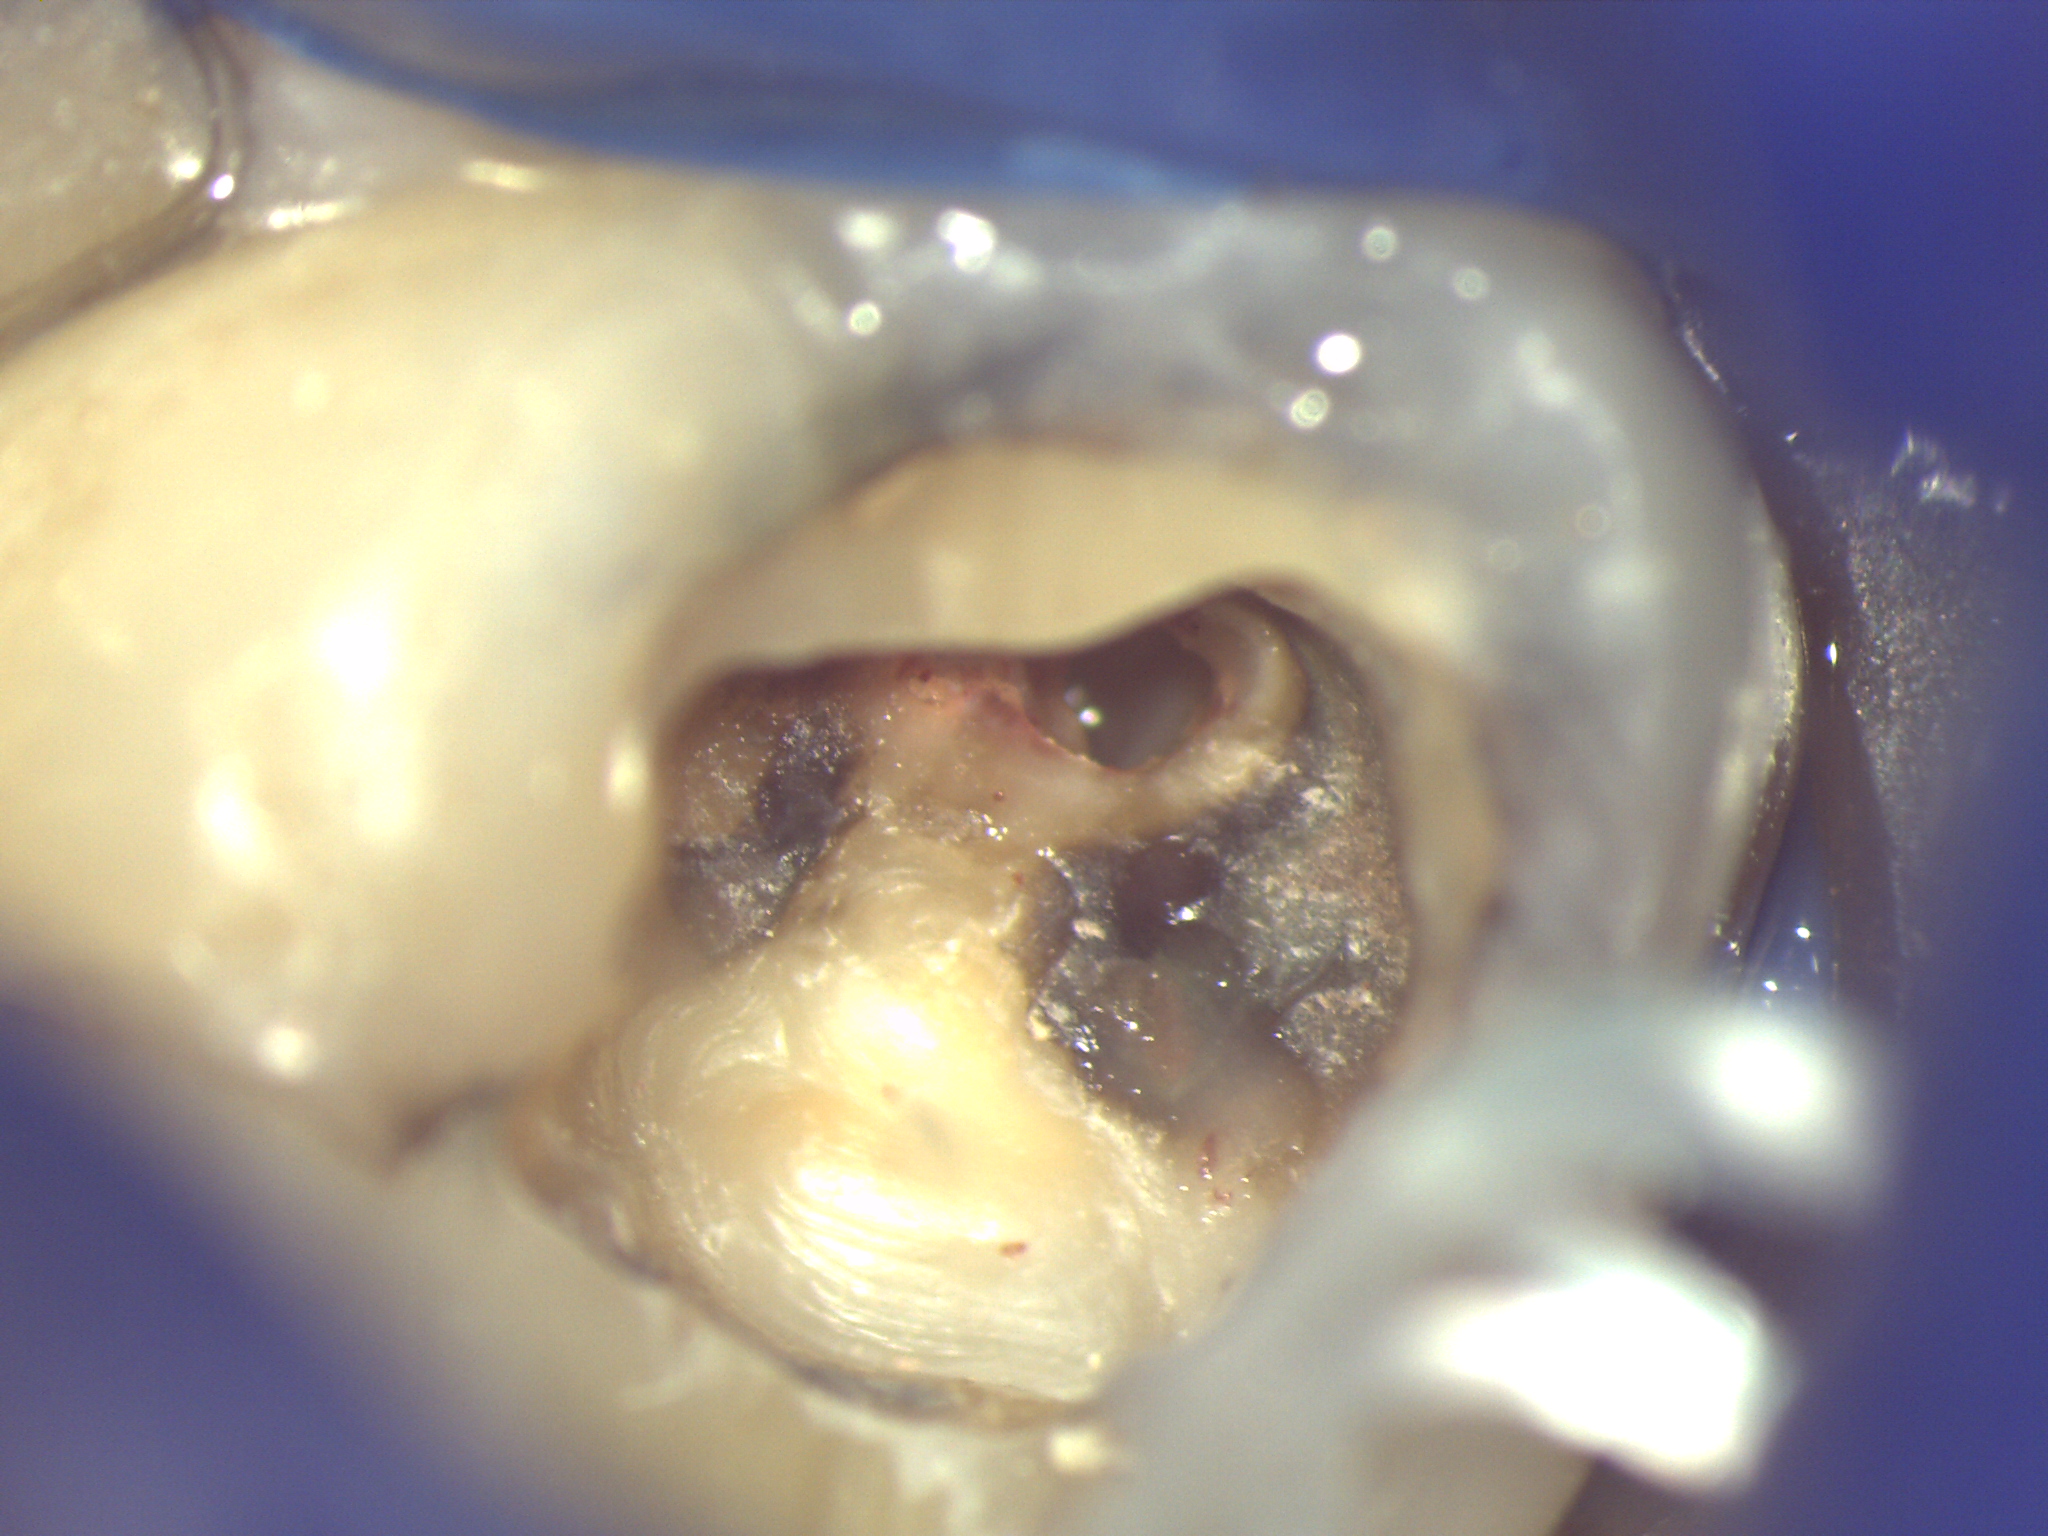

当院では歯の根本である根管治療を大事に考えておりますのでラバーダムをかけたり、マイクロスコープなどで拡大して丁寧に行っております![]()

拡大すると色々なものが見えてきて成功率が上がります。